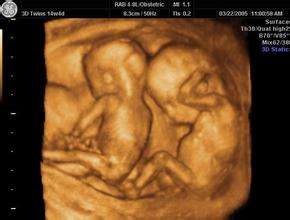

陈万桃和家属都觉得难以置信,要知道在生产之前,赵洋洋曾经在上海和自贡的3个医院做过多次产检,并且在生产之前的B超检查中还认为是“双活胎”, 医院提供的“自贡中城医院彩超报告单”上,有非常明确的胎1、胎2数据,并且在自贡中城医院术前小结中也有“宫内双活胎”的叙述。那么问题来了,另外一胎到底去哪了?

对此,医院的解释是,在赵洋洋做过了四维彩超之后,另一个胎儿可能会被吸收了。并且,医院说在产前的B超检查是看错了,B超检查的时候在产妇的左下腹出现圆形强回声反射,再加上之前孕妇在上海嘉定区妇幼保健院中的检查报告中显示是双胞胎,赵洋洋自己也说是双胞胎,因此,B超医生就在报告上写下了“宫内双活胎”的结论!

假如说,孕妇在产前只做过一次B超出现了错误,那还有可能,现在是产前最起码做了五六次的B超,并且还是在不同的医院。如果说有一个医生发生了失误,难道所有医生都发生了失误?而且,这个失误是一个胎儿和两个胎儿的差别。并且,在四维彩超的时候,B超单子上会有关于胎儿血流、心脏、四肢、五官、心脏等所有的数据,难道这些都是医生胡编乱造的?